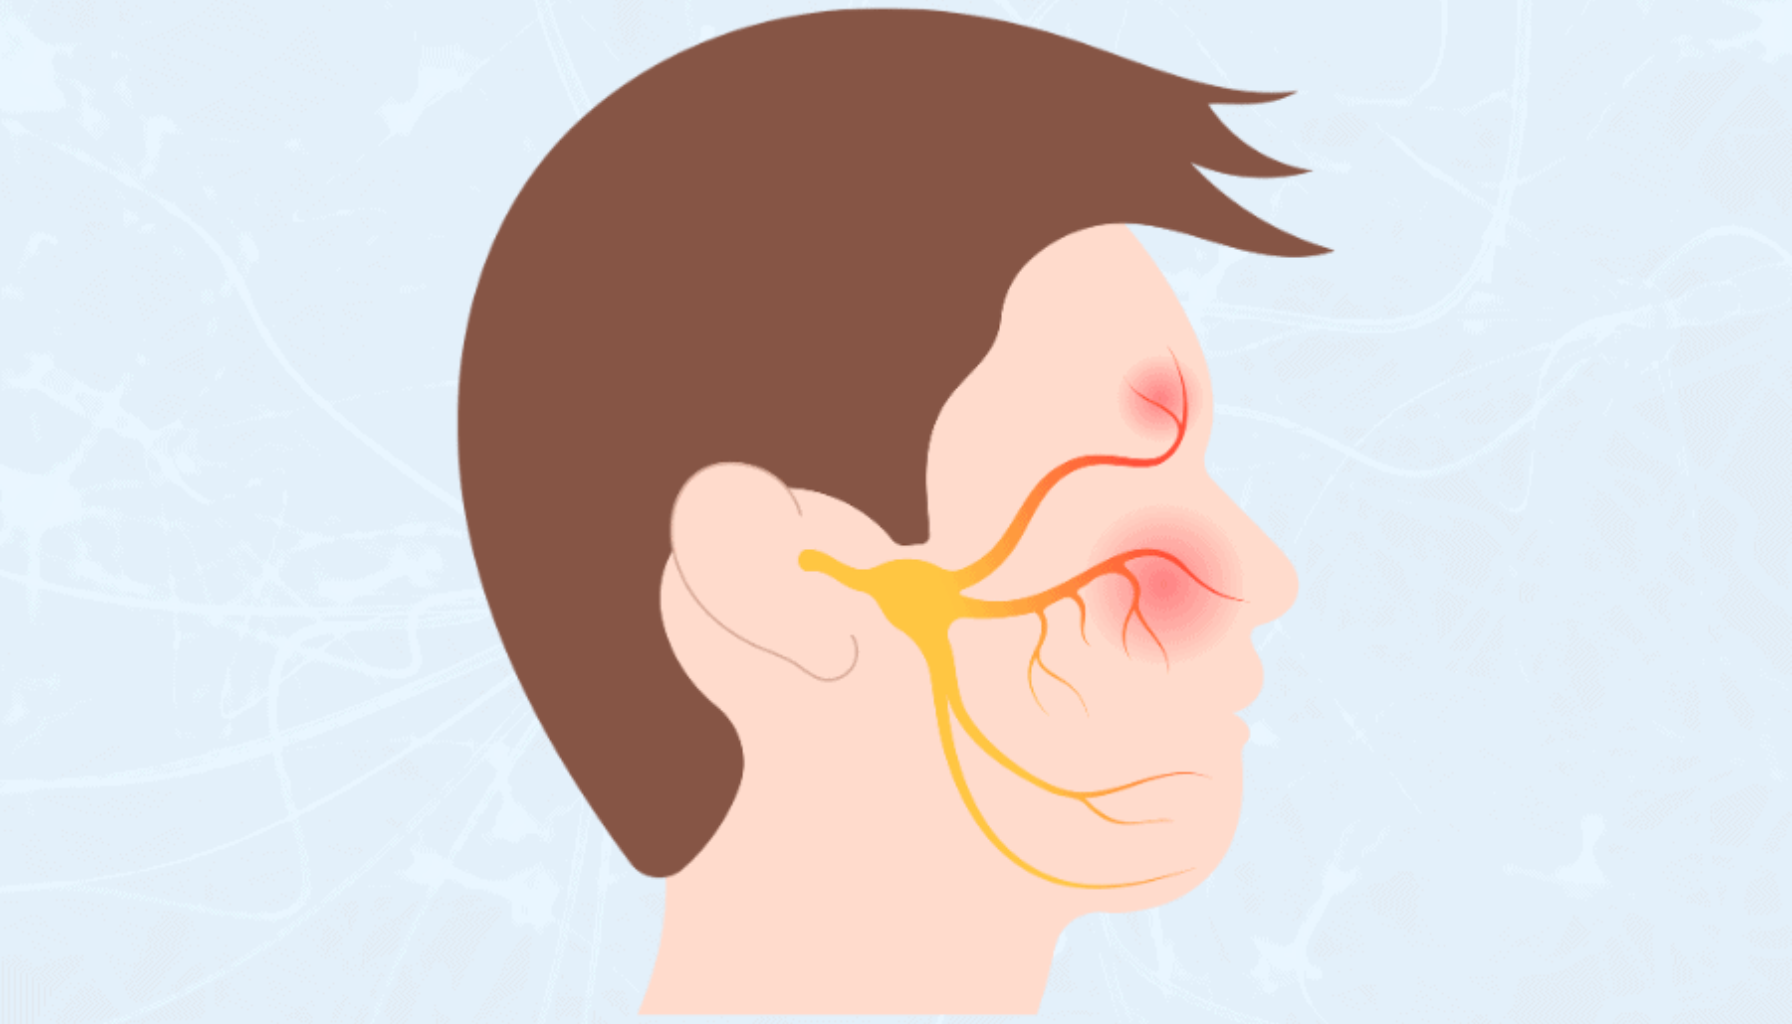

Et tannimplantat er en moderne og avansert løsning for å erstatte tapte tenner. De består vanligvis av tre hovedkomponenter: en titanimplantat som fungerer som en kunstig tannrot, en distanse som forbinder implantatet med kronen, og en porselenskrone som ser ut og føles som en naturlig tann. Titanimplantatet settes kirurgisk inn i kjevebenet, hvor det integreres med benvevet gjennom en prosess kjent som osseointegrasjon. Denne prosessen sikrer at den kunstige roten blir solid og stabilt, noe som gjør at det kan tåle de daglige kreftene som påføres under tygging og biting.

Når planleggingen er fullført, vil det første kirurgiske trinnet være innsetting av implantat i kjevebenet. Operasjonen utføres under lokalbedøvelse, og prosedyren er vanligvis ganske komfortabel for pasienten. Etter operasjonen kjeven få tid til å integreres rundt implantatet gjennom osseointegrasjon, som kan ta lang tid. Opp til flere måneder.